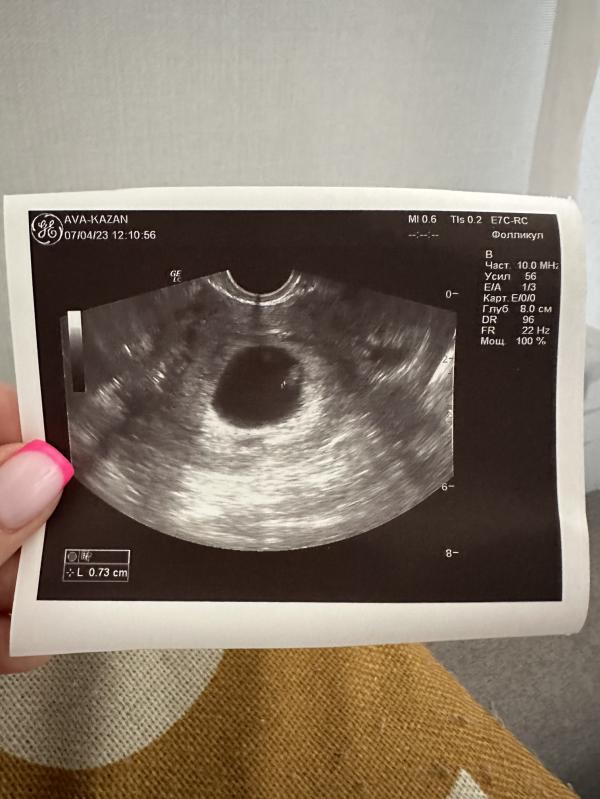

6 недель 3 дня, эмбриончик растет, сердечко бьется) Договорились на еще одно узи через две недели, а потом попрощаемся с репродуктологом и пойду вставать на учет в ЖК🤞🏻про выделения так врач ничего и не говорит, отслойки по узи нет

07.04.2023